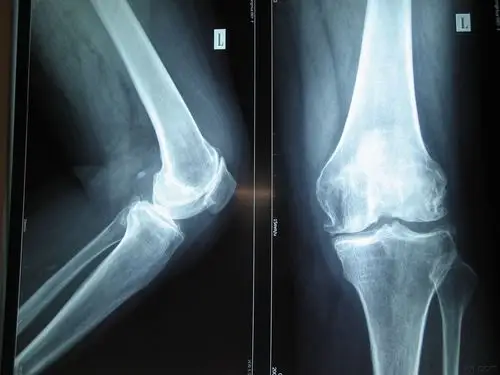

左小腿骨折x线片

左腿ap外侧骨折x线片.